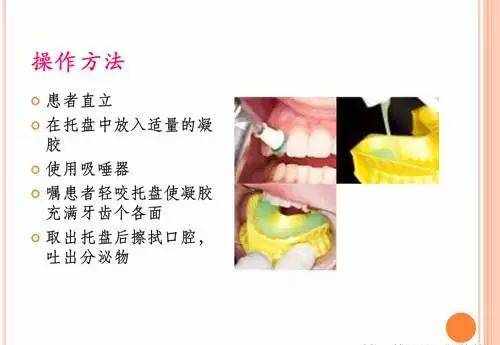

(1)氟凝胶

(2)氟化泡沫

(3)氟保护漆

通过涂氟保护漆,让出现了脱矿的牙齿(早期蛀牙的表现)得到了明显的修复。